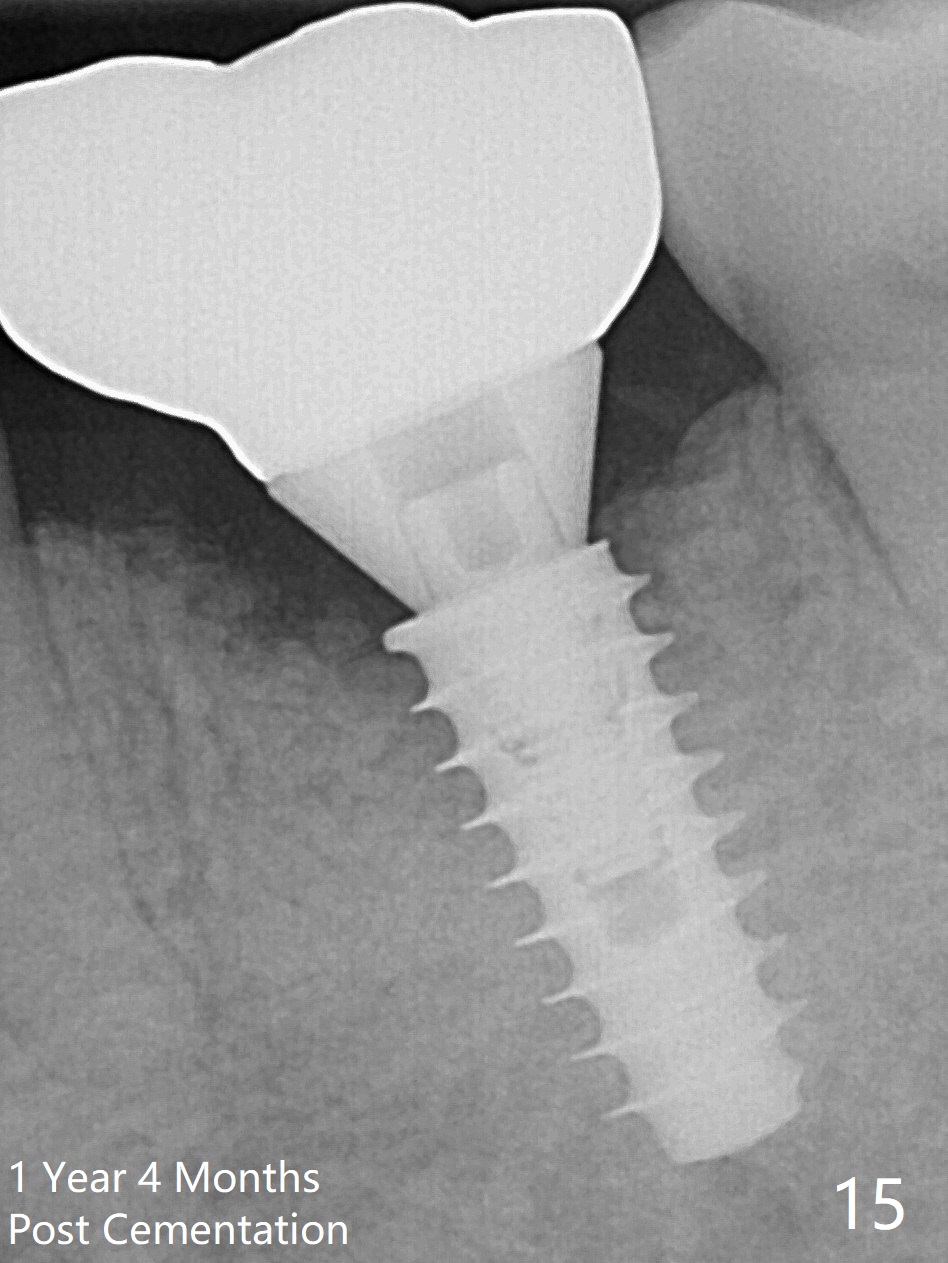

There is a new pattern of bony trabeculae around the implant 4.5 months postop (Fig.14). Bone density increases 1 year 4 months post cementation (Fig.15).